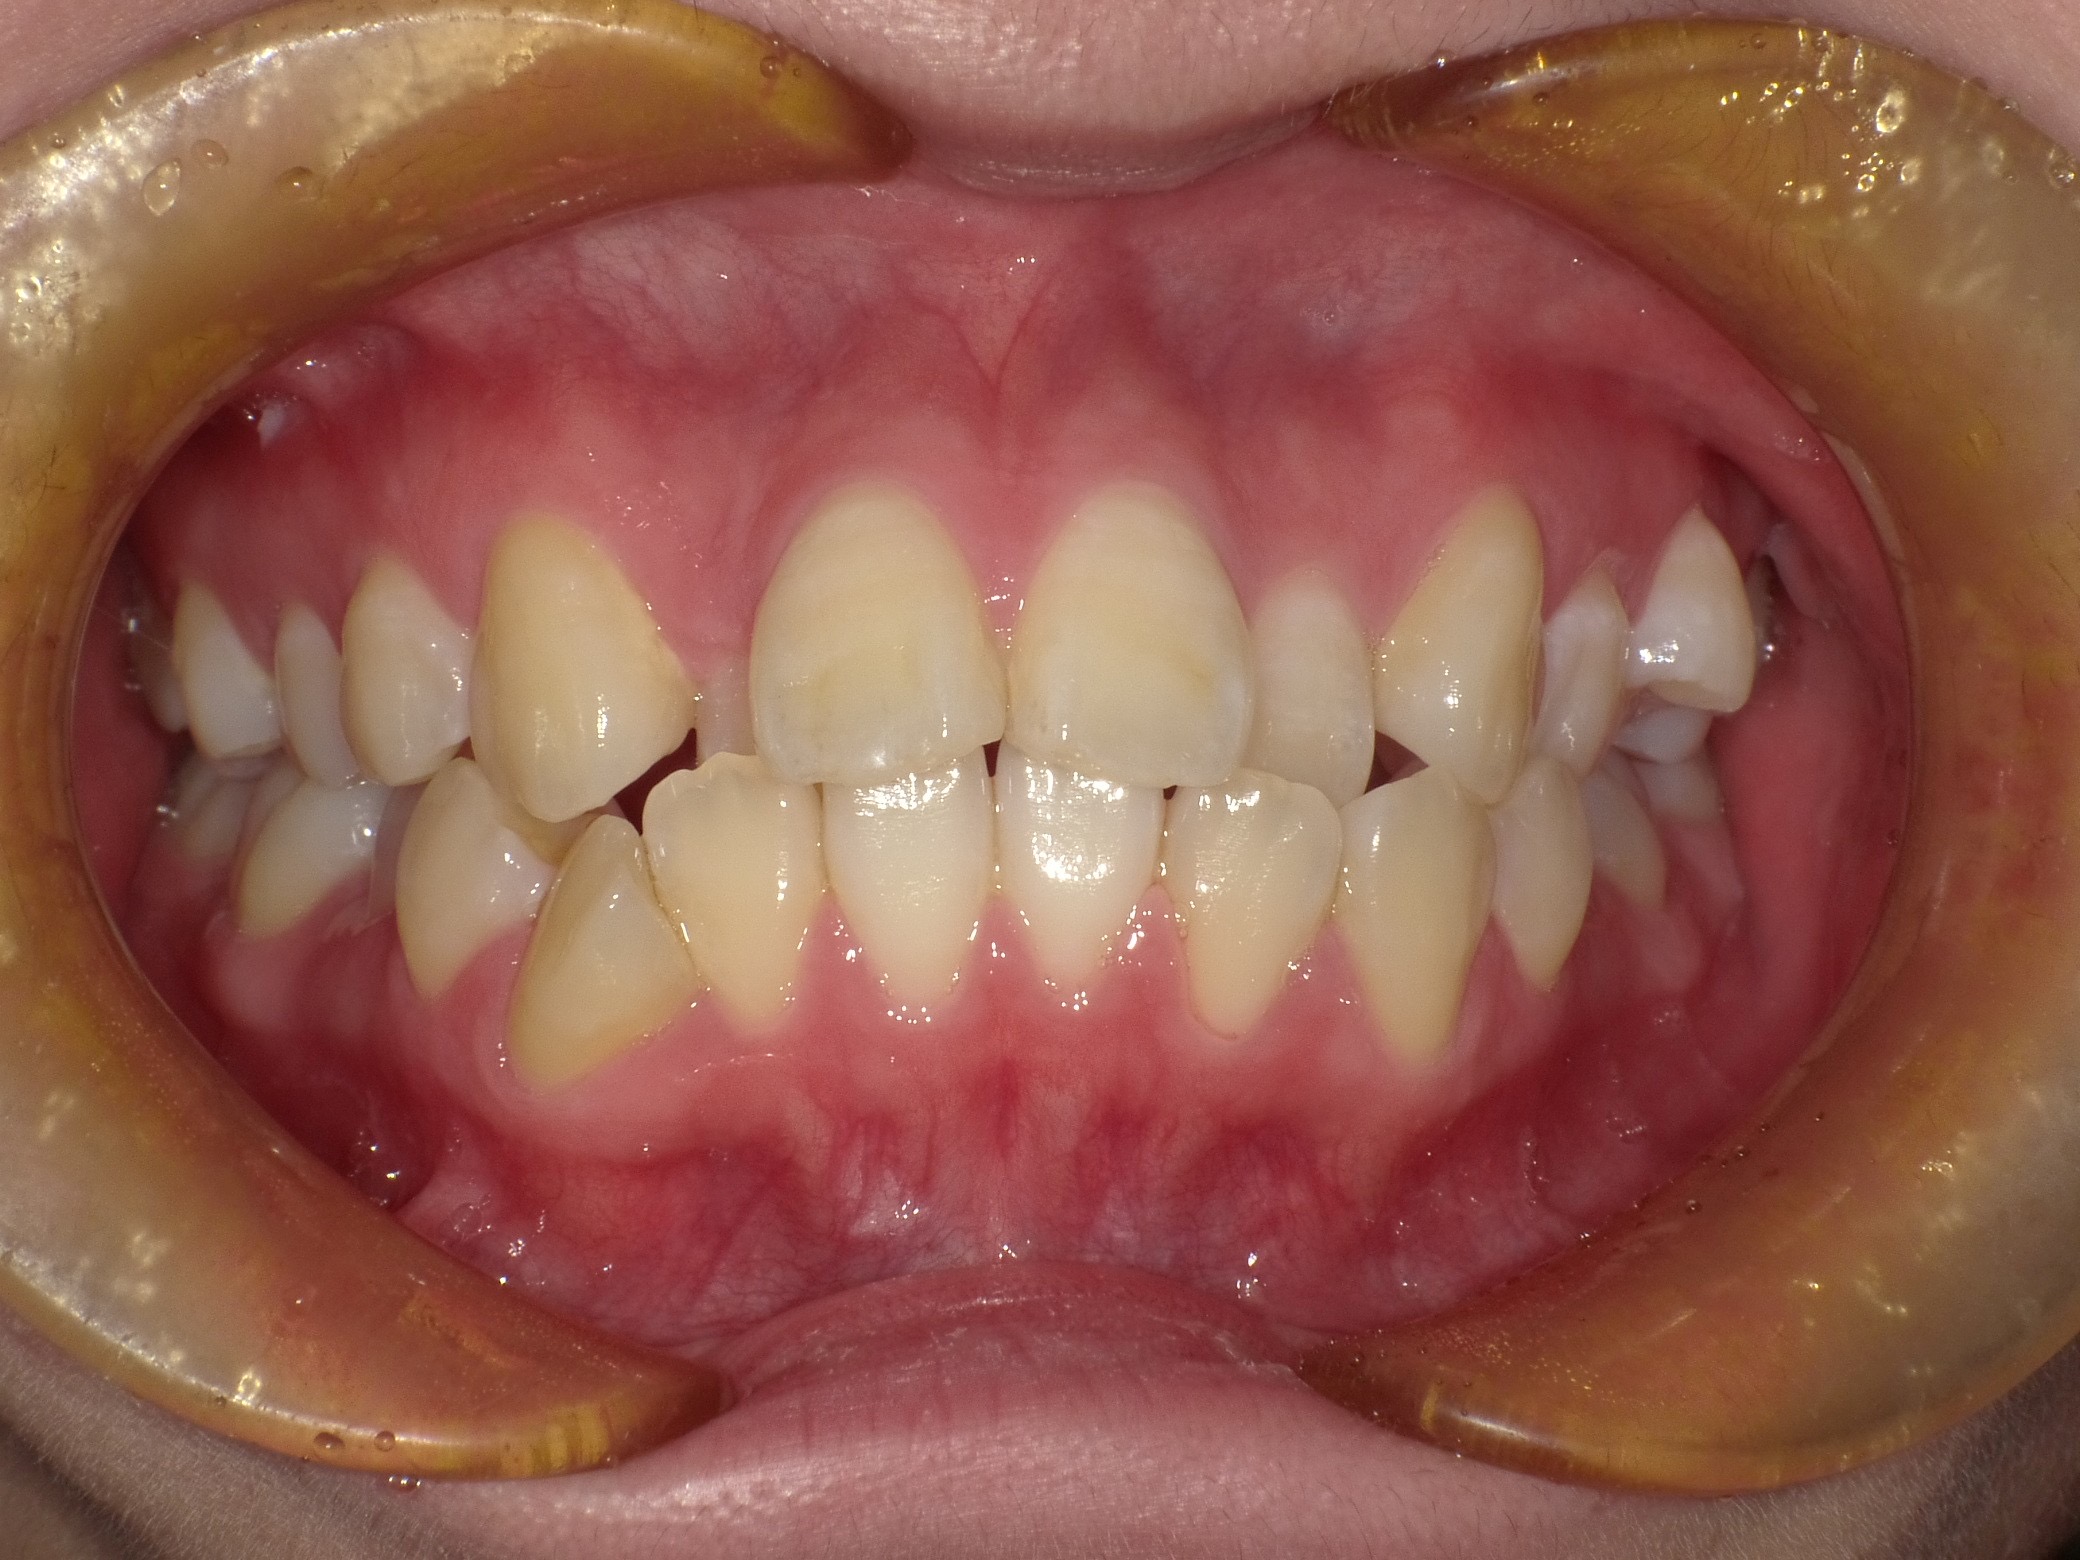

症例②

症例2_治療前 症例2_治療後

年齢・性別 31才・男性

治療方法 ブラケット矯正

治療期間 3年

治療総額 850,000円

特記事項 抜歯あり(4本抜歯)